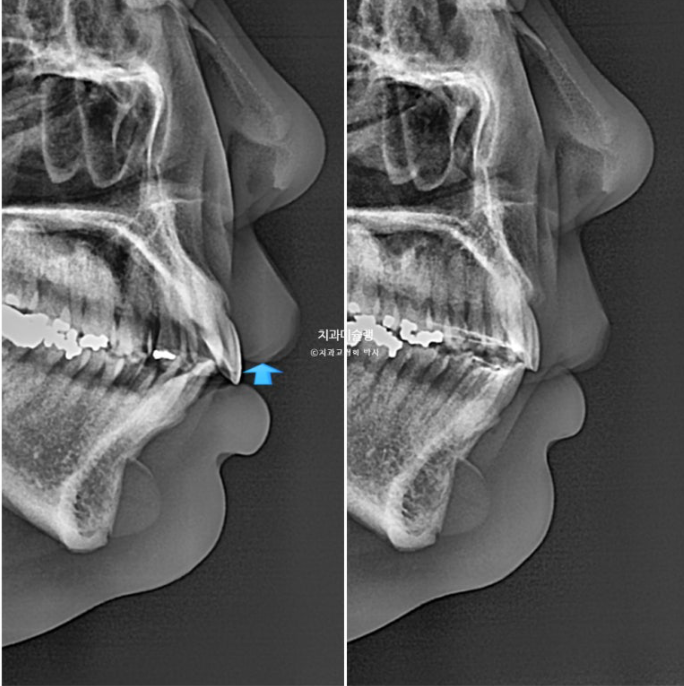

If we compare the before-and-after X-rays,

The upper front teeth were intruded by 2 mm. Thanks to that, gum exposure when smiling decreased, and the gummy smile was resolved.

The front teeth moved back a great deal, but the key point is that they did not become over-inclined inward.

During the three-year treatment period, root resorption occurred in the upper front teeth.

Because the amount of backward movement of the front teeth was so large, and because we focused on moving the roots backward more than the crowns to prevent excessive inward tipping, this was unavoidable.

The root parallelism is good.